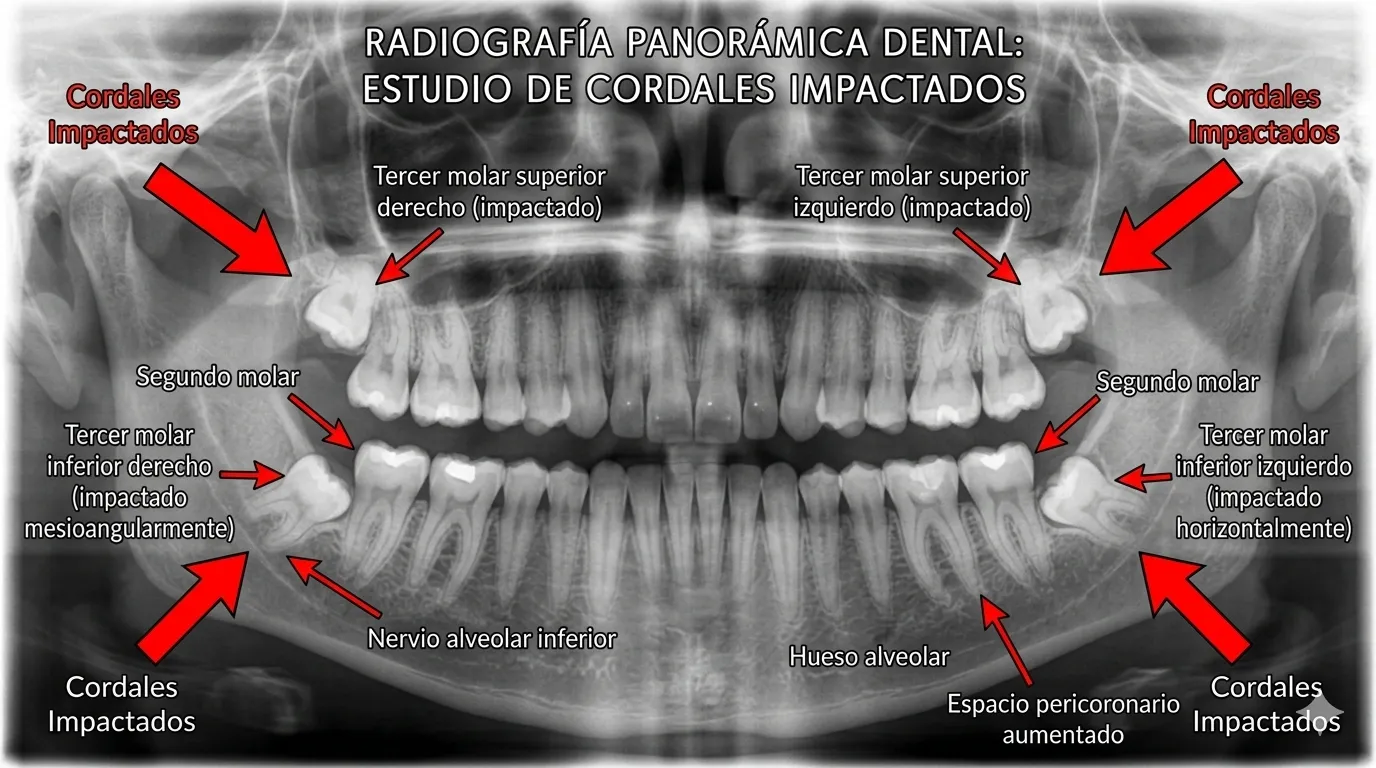

En Bienestar Dental, nuestros especialistas en cirugía oral evalúan cada caso con radiografías panorámicas para determinar si tus muelas del juicio necesitan tratamiento o pueden quedarse tranquilamente.

En aproximadamente el 85% de las personas no hay espacio suficiente para que las cuatro muelas del juicio erupcionen correctamente. Cuando quedan atrapadas en el hueso, se denominan muelas impactadas y pueden adoptar distintas posiciones:

Impactación vertical

El diente apunta hacia arriba pero no tiene espacio para salir completamente

Impactación horizontal

El diente está completamente acostado, empujando al molar vecino

Impactación mesioangular

Inclinada hacia el diente de adelante — la más frecuente

Impactación distoangular

Inclinada hacia atrás, difícil de extraer